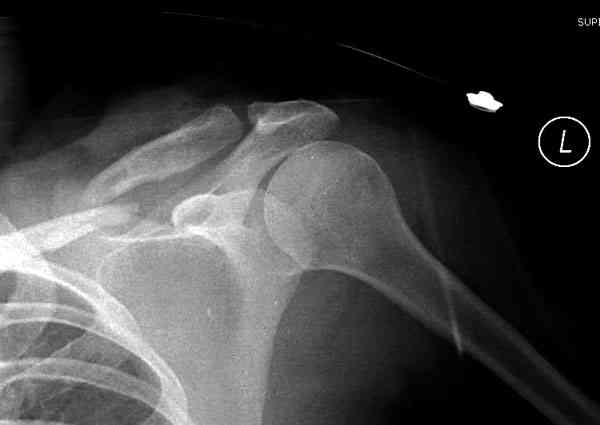

ГГШ> Результат стационарного лечения приведен на рентгенограмме (Xray_3).

Это картинка то есть через неделю после травмы, при выписке? Более чем приемлемо.

Травма амбулаторная, смещение изначально было допустимым, но можно было и подправить, только мы у старших детей применяем шинно-гипсовую повязку. В данном случае репозиция положения не улучшила, на последних рентгенограммах положение отломков удовлетворительное. С уважением, А.В. Шахин

2) стояние фрагментов при выписке идентично таковому при пступлении - с выраженным смещением

Уважаемая Г.В. Полностью согласен с Вашим постом.Закрытая репозиция и кольца Дельбе отлично зарекомендовали себя за 35 лет практики. В обсуждаемом случае представленные Р-граммы сами говорят за себя, 1 снимок (до лечения) и 3 снимок (после лечения) абсолютно идентичны, 2 снимок сделан в несколько иной позиции.Как говорится "комментарии излишни". Согласитесь, что результат лечения мог бы быть и лучшим.